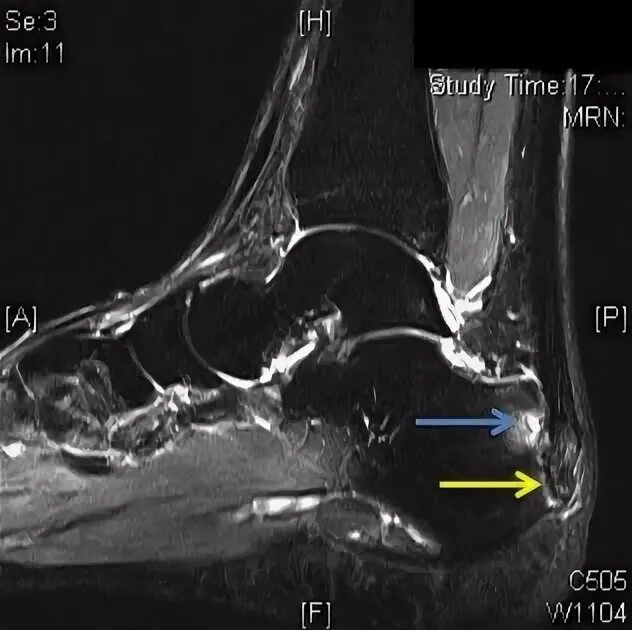

Мрт ахиллового сухожилия